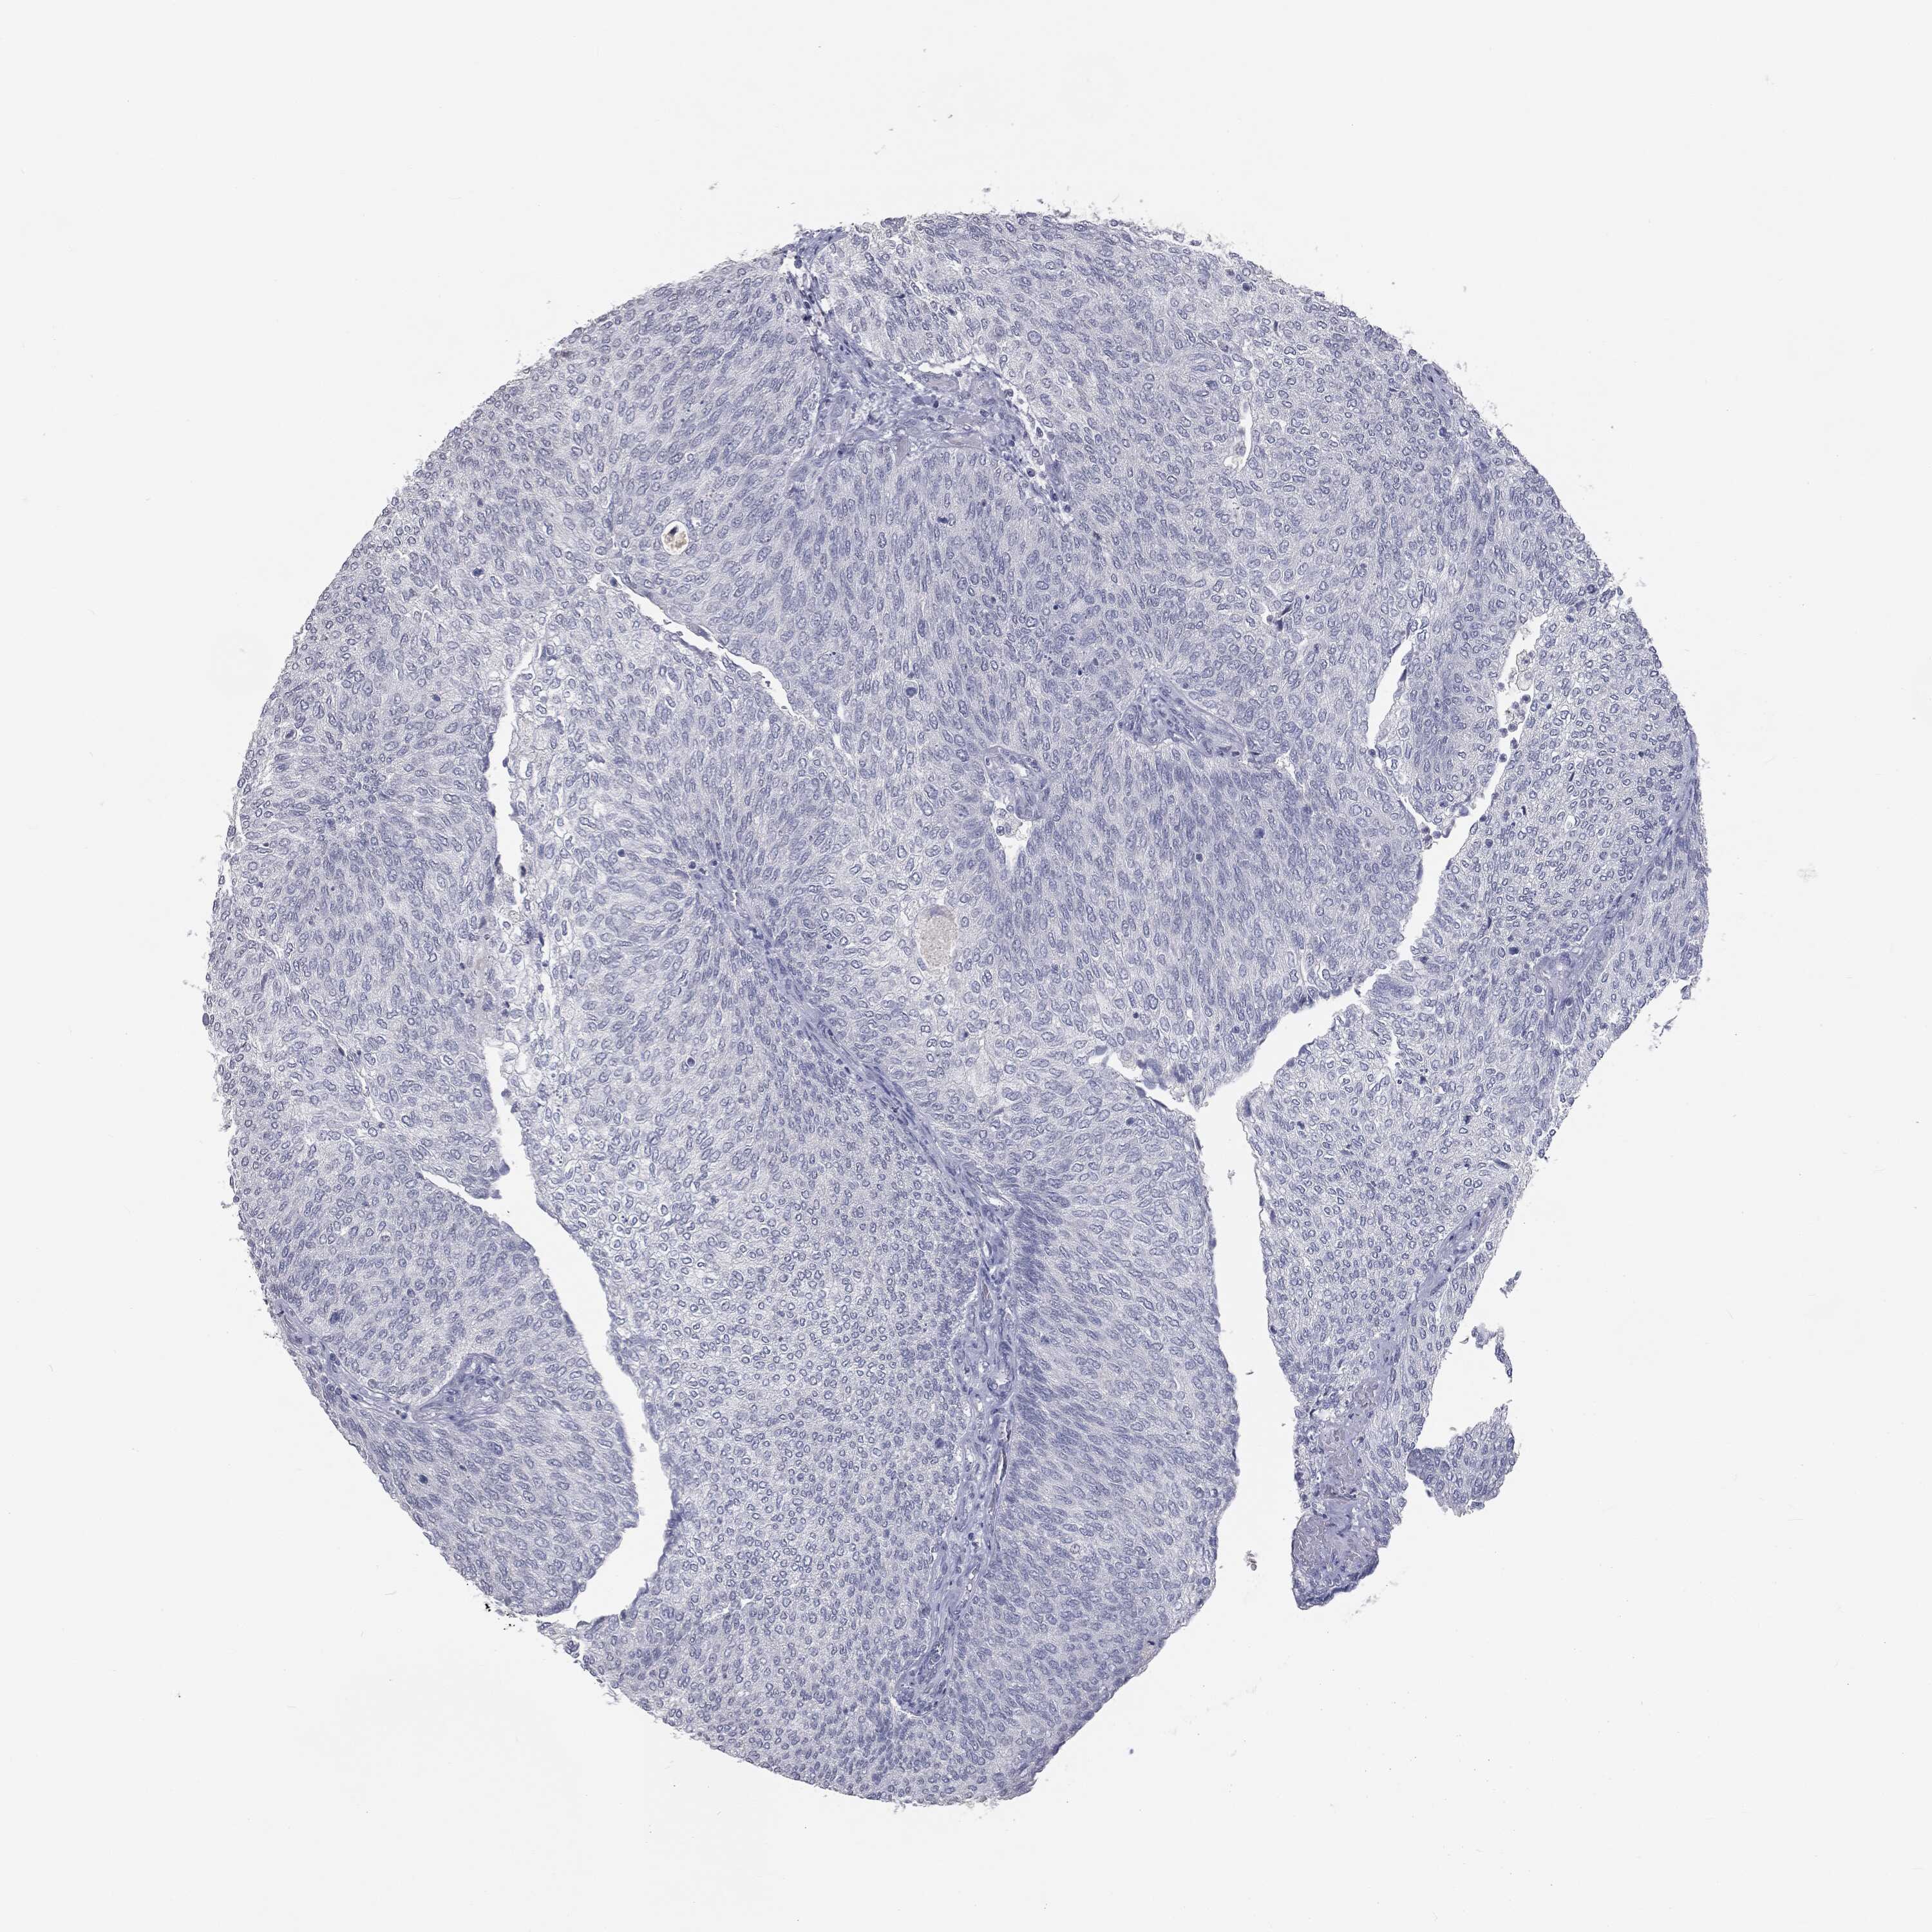

UROTHELIAL CANCER - Protein expressioni

A mouse-over function shows sample information and annotation data. Click on an image to view it in a full screen mode. Samples can be filtered based on level of antibody staining by selecting one or several of the following categories: high, medium, low and not detected. The assay and annotation is described here.

Antibody stainingi

Antibody staining in the annotated cell types in the current human tissue is reported as not detected, low, medium, or high, based on conventional immunohistochemistry profiling in selected tissues. This score is based on the combination of the staining intensity and fraction of stained cells.

Each image is clickable and will lead to virtual microscopy that enables deeper exploration of all samples and also displays staining intensity scores, fraction scores and subcellular localization as well as patient and tissue information for each sample.

Antibody HPA045153

Antibody CAB080138

Urothelial carcinoma, High grade

Urothelial carcinoma, NOS

Urothelial carcinoma, Low grade